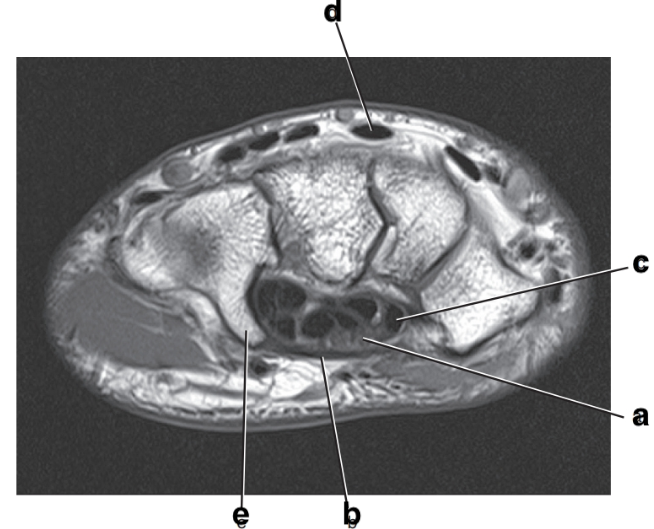

Hook of the hamate

Scaphoid

c